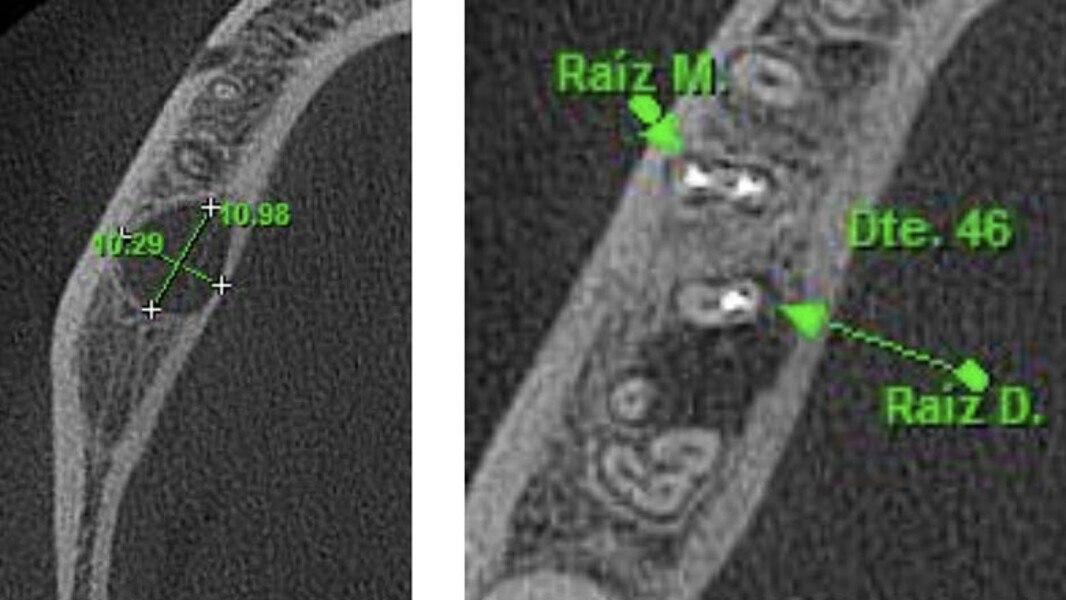

Figura 1. Inclinación de la raíz distal del primer molar inferior derecho hacia lingual. Ubicada aproximadamente a 10 mm de la cortical ósea vestibular, lo que hace imposible hacer el abordaje quirúrgico a través de microcirugía.